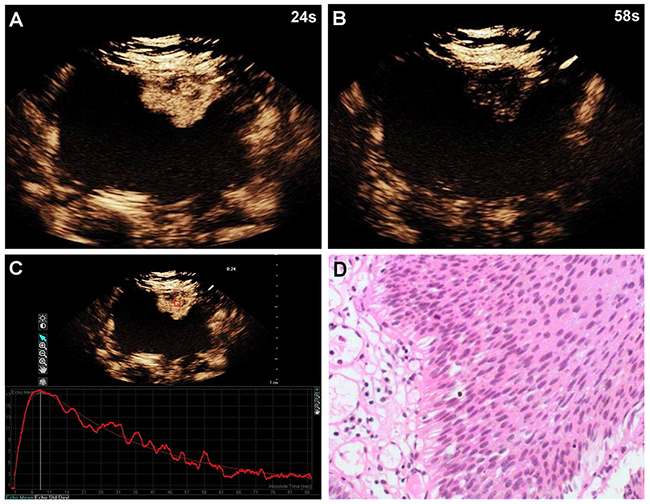

Of the 96 histopathological lesions, 54 were cases of high-grade urothelial carcinoma (4 Ta, 44 T1, 6 T2) and 42 were low-grade urothelial carcinomas (40 Ta, 2 T1) (Table 1). CEUS patterns were divided into three types: type I, fast wash-in and fast wash-out, 86% (36/42) of low-grade urothelial carcinomas showed quick enhancement in and around the lesions, and regression occurred earlier than in adjacent normal bladder wall (Figure 1); type II, slow wash-in and fast wash-out, 7% (4/54) of high-grade tumors and 5% (2/42) of low-grade tumors showed slow enhancement, and regression occurred earlier than in adjacent normal bladder wall; and type III, fast wash-in and slow wash-out, 85% (46/54) of high-grade urothelial carcinomas were quickly enhanced from the central tumor to its periphery, and regression occurred later than in adjacent normal bladder wall (Figure 2). Comparisons of all parameters of the gamma variate are shown in Table 2. There were no differences in AT and TTP between high- and low-grade bladder tumors (P>0.05). High-grade tumor PIs were greater compared to low-grade tumors, and low-grade tumor WTs were less than those of high-grade tumors (P<0.05). Combined enhancement patterns for high- versus low-grade bladder tumors are shown in Table 1.

Figure 1: A 60-year-old woman with low-grade bladder cancer on the anterior bladder wall. CEUS shows strong and fast lesion enhancement during the late arterial phase (24 sec) (A), and complete wash-out during the venous phase (58 sec) (B). Time-intensity curve shows fast wash-in and fast wash-out, and lower PI (C). Surgical specimen confirming low-grade bladder cancer (hematoxylin & eosin staining, original magnification ×100) (D).